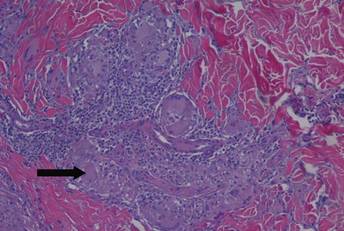

A healthy 44-year-old man presented with a several month history of elevated, erythematous to yellow, anesthetic papules and plaques on the trunk (Figure 1). No other systemic symptoms were noted. Biopsies of multiple skin lesions showed noncaseating granulomas with preferential extension in a perineural pattern and tracking along the arrector pili muscle (Figure 2). The cutaneous nerves appeared to be slightly enlarged. The patient reported a history of living in Louisiana and growing up with armadillos in the backyard, often filling the holes that they dug, but he denied having direct contact with or eating armadillos. In childhood, the patient traveled across the border to Mexico a few times but only for the day. He spent several months in the Middle East (ie, Diego Garcia, Saudi Arabia) more than 10 years prior to presentation, and he spent 2 weeks in Korea approximately 2 years prior to presentation but did not travel off the US air base. He had never traveled to South America or Africa. The clinical and histopathologic findings were consistent with Hansen disease (leprosy) and were determined to be tuberculoid in type given the limited clinical presentation, tuberculoid granulomas on biopsy, and no visible organisms on histopathologic analysis.

Figure 1. Granulomatous cutaneous reversal reaction on the trunk. Figure 2. Photomicrograph demonstrating a dermal infiltrate of noncaseating granulomas composed of epithelioid histiocytes, lymphocytes, and giant cells with a perineural granuloma (arrow)(H&E, original magnification ×200). |